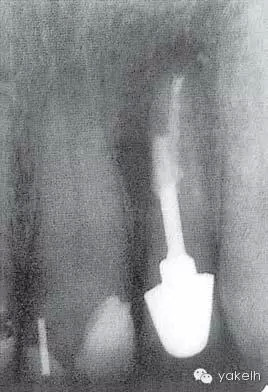

¤¤在征得患者同意后,最終選擇根管外科手術(shù)修復(fù)穿孔。局麻下翻開三角形全厚黏骨膜瓣,充分暴露骨和根面;使用刮匙去除穿孔上覆蓋的肉芽組織,暴露穿孔和樁(圖5.4.2a);使用外科專用渦輪手機(jī)配以金剛砂小球鉆,去除樁的尖端;使用超聲銼去除根管末端的牙膠,并進(jìn)行根管預(yù)備(圖5.4.2b);預(yù)備后的根管與穿孔部位使用IRM嚴(yán)密封閉(圖5.4.2c);瓣復(fù)位、縫合固定,拍攝術(shù)后X線片(圖5.4.3a);3天后拆線。

圖5.4.3(a)22術(shù)后X線片,顯示穿孔修復(fù)、根管末端充填。